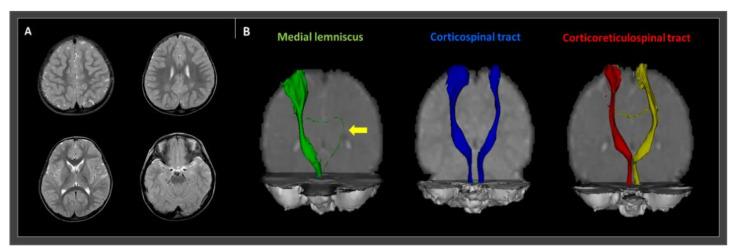

We describe the successful application of hinged ankle-foot orthoses (AFOs) in a cerebral palsied (CP) patient with gait instability due to a disrupted medial lemniscus (ML). The patient was a 27-month-old male CP child with gait instability who presented with reduced knee flexion and ankle dorsiflexion, with severe genu recurvatum on his right lower extremity during gait. The patient had no motor weakness or spasticity. Conventional magnetic resonance imaging (MRI) revealed no definite abnormal lesion. However, diffusion tensor tractography (DTT) showed disruption of the left ML, consistent with right hemiplegic symptoms. The integrity of the major motor-related neural tracts, including the corticospinal and corticoreticulospinal tracts, was preserved. We considered that the patient's abnormal gait pattern was related to the disrupted ML state. We applied hinged AFOs, which immediately resulted in a significantly stabilized gait. The angles of knee flexion and ankle dorsiflexion increased. Our findings indicate that the application of hinged AFOs could be a useful therapeutic option for CP patients with gait instability related to ML disruption. In addition, we showed that DTT is a useful tool for identifying the causative brain pathology in CP patients, especially when conventional brain MRIs show no specific lesion.

我们描述了带铰链的踝足矫形器(AFO)在一名因内侧丘系(ML)中断而步态不稳的脑性瘫痪(CP)患者中的成功应用。该患者为一名27个月大的男性CP患儿,步态不稳,表现为膝关节屈曲和踝关节背屈减少,在步态期间右下肢有严重膝反张。患者无运动无力或痉挛。常规磁共振成像(MRI)未显示明确的异常病变。然而,弥散张量纤维束成像(DTT)显示左侧ML中断,与右侧偏瘫症状一致。包括皮质脊髓束和皮质网状脊髓束在内的主要运动相关神经束的完整性得以保留。我们认为患者异常的步态模式与ML中断状态有关。我们应用了带铰链的AFO,这立即导致步态显著稳定。膝关节屈曲和踝关节背屈角度增加。我们的研究结果表明,对于与ML中断相关的步态不稳的CP患者,应用带铰链的AFO可能是一种有用的治疗选择。此外,我们表明DTT是识别CP患者脑病因病理的有用工具,尤其是当常规脑MRI未显示特定病变时。